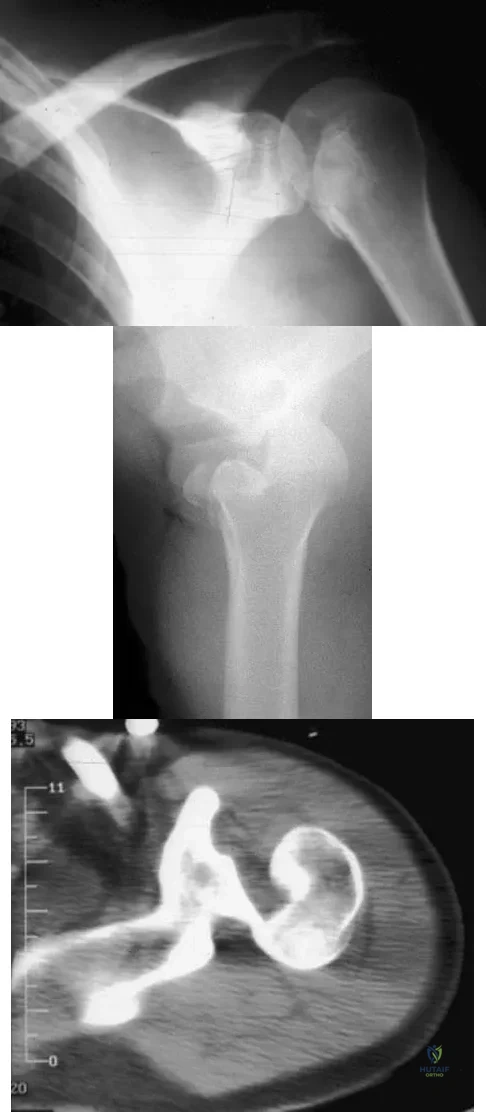

A 21-year-old patient has had pain and a marked decrease in active and passive shoulder motion after having had a seizure 2 months ago as the result of alcohol abuse. Current AP and axillary radiographs and a CT scan are shown in Figures 26a through 26c. Management should consist of

Detailed Explanation